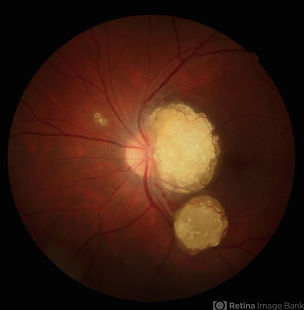

APMPPE

Acute Posterior Multifocal Placoid Pigment Epitheliopathy

Typical features include, M = F, 20-30s, bilateral and acute onset, variable viral prodome, Classic WDS symtpoms, resolves in weeks-months, recurrence is rare, multifocal flat gray-white placoid lesions at the level of the posterior pole. RPE improving within 1-2 weeks, and can have disc swelling. Mild vitreous cells, no CNV, good prognosis but can have RPE mottling and depigmentation.